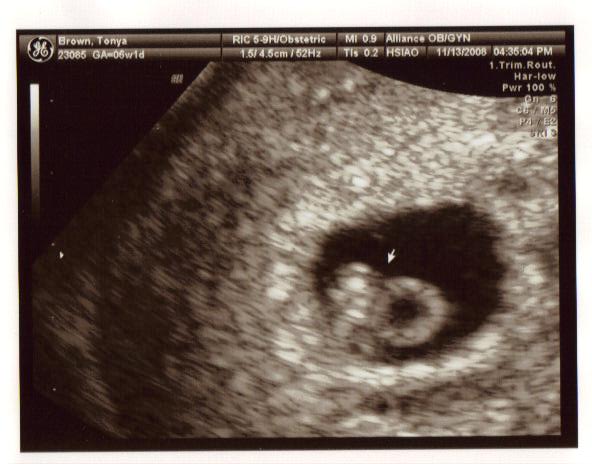

November 13, 2008

This was the biggest day in our lives so far, we were going to hear our baby(ies)’s heart beat for the very first time. Poor Tanya, she has been up all night sick and coming to the appointment, when she would rather just stay in bed, was miserable for her. I felt so sorry for her. Jeremy and I couldn’t contain ourselves, we were so anxious to find out how many babies we are expecting and hoping for that sign of life – healthy heart beat.

And there it was, faint but healthy and right on target – one baby, one heart beat! It was an amazing feeling. We saw and heard our baby for the very first time.

Tanya had some blood in her uterus, visible on the ultrasound but the doctor didn’t seem to be concerned about it, he said that it happens. She just needs to take it easy and it will disappear.

We were given a due date of July 8, 2009.

Our embryo is officially a PEANUT.

Here the arrow is pointing at PEANUT and its heart beat.

Here the arrow is pointing at the yolk sac that PEANUT is living off of.